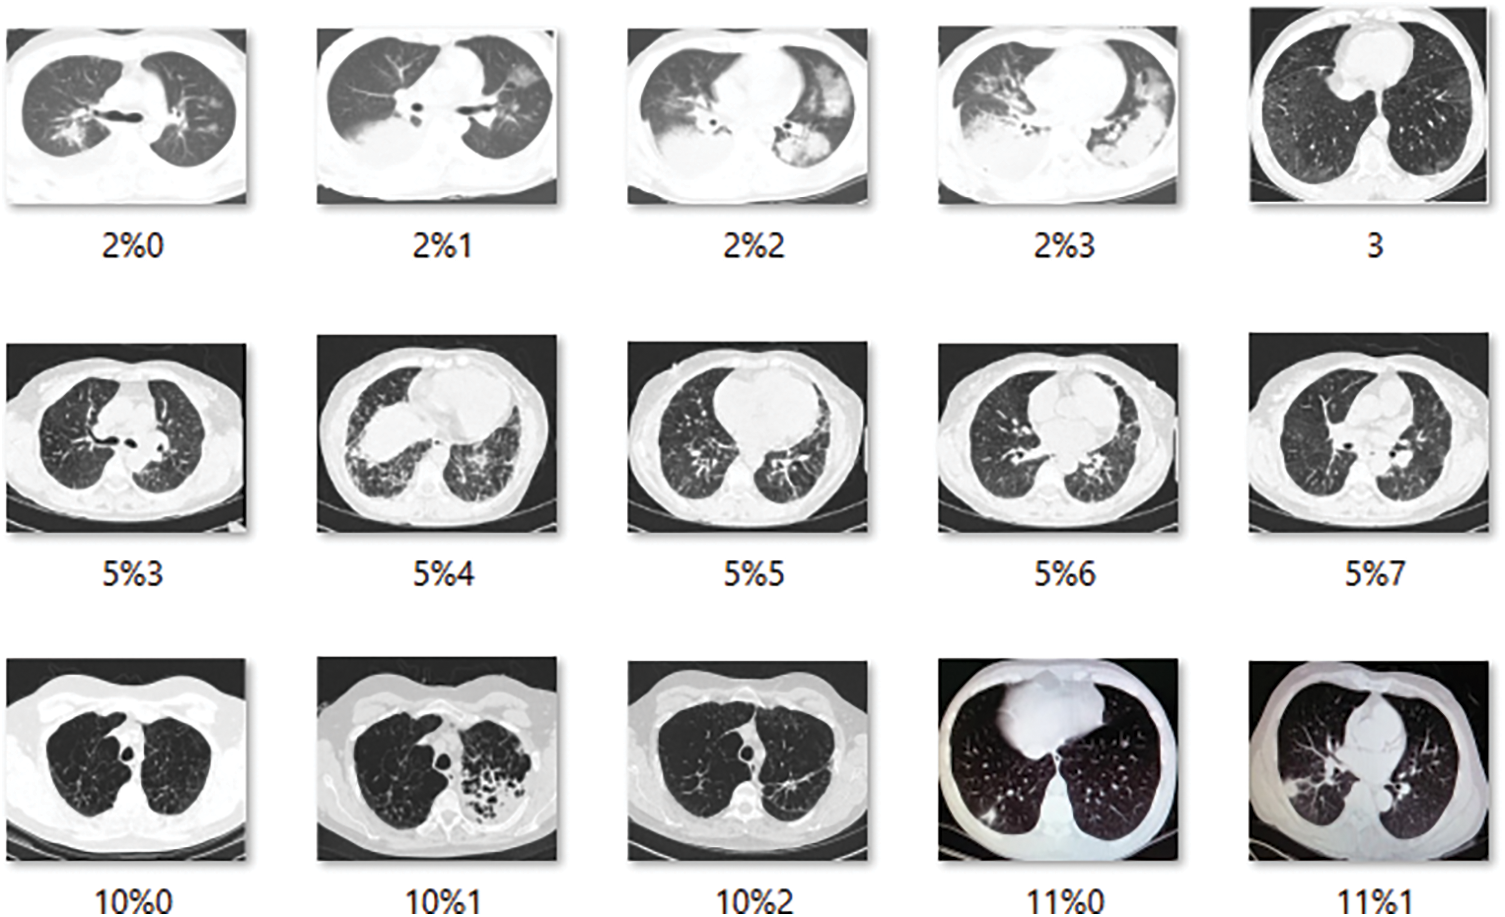

To begin with the classification model, we transform all of the digital images into NumPy arrays so that the read files can be readily transferred to various computing environments. In this study, we use Google Colab to conduct our research. We utilized the computer vision (CV) module of Python to read the images and convert them to digital images. Let’s take a look at the dataset that we have just created now that we have extracted all of the required images from the various sources that were open for separate examination by the researchers. Furthermore, we are only considering similar types of data contained in all three groups of X-Ray images. The X-Rays images provide a total of 8027 images for the study of the models. Below is a sampling of each of the images. Fig. 1 shows image samples of COVID-19 dataset, while Fig. 2 presents image samples of Pneumonia dataset.

Figure 1: COVID-19 database. 15 images showing the COVID-19 infections